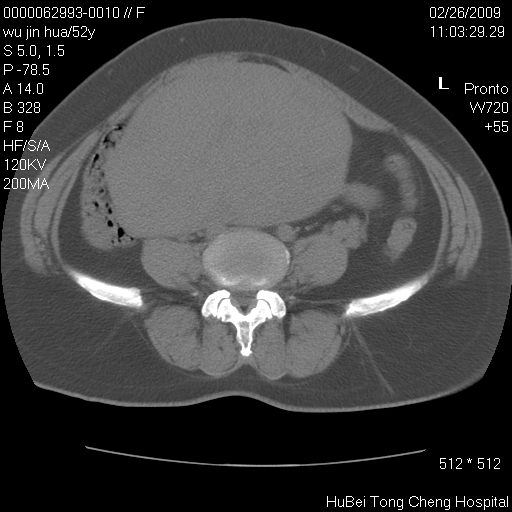

依据平片“腰椎退行性改变”报告,作椎间盘ct扫描时发现:

影像表现:盆腹腔巨大占位,内密度均匀,边界清,未做强化。

来源:考虑来源于腹膜后肿瘤。

性质:以肉瘤可能性大。